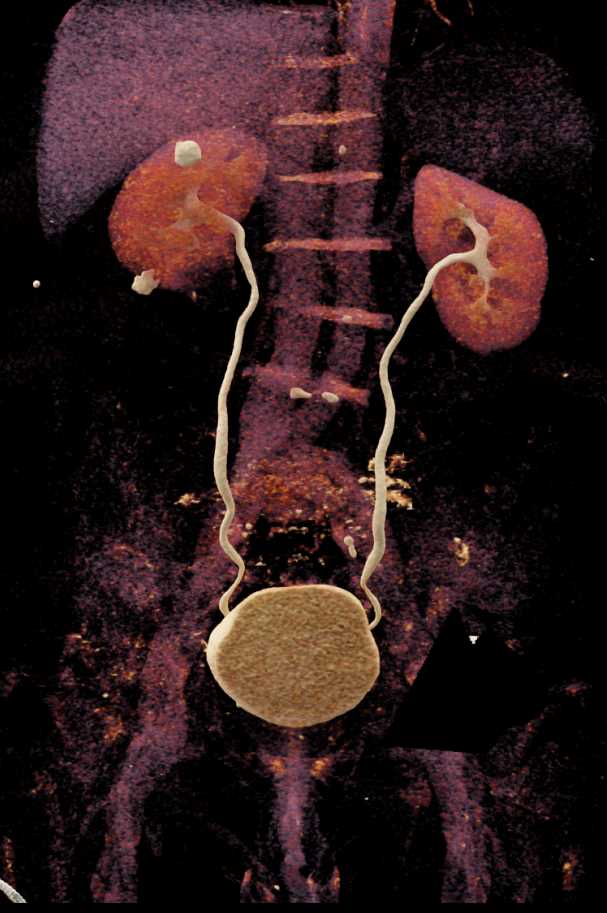

Water Density Renal Cyst . As you get older, cysts can form on the. Simple cysts are individual cysts that form on. Simple cysts and polycystic kidney disease. Renal cysts are sacs of fluid that form in the kidneys. A simple kidney cyst is a pocket of fluid that originates from the surface of the kidney and is contained by a thin wall. One or more simple cysts may form within the. Kidney cysts (renal cysts) are usually small, round sacs that have a thin wall and contain a watery fluid. But more often, kidney cysts are a type. You might develop one cyst or. There are two types of kidney cysts: Kidney cysts can occur with disorders that may impair kidney function. Kidney cysts are round pouches of fluid that form on or in the kidneys.

High Density Renal Cyst Left Kidney Kidney Case Studies CTisus CT